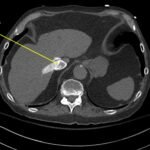

A 78-year-old gentleman presented to the emergency department (ED) for palpitations and dizziness. He had a complicated medical history including atrial fibrillation (AF), recently status post a Watchman procedure, oxygen-dependent chronic obstructive pulmonary disease (COPD), and heart failure with preserved ejection fraction (HFpEF). Point-of-care ultrasound (POCUS) revealed the presence of an intracardiac right atrial thrombus. Computed tomography (CT) angiography confirmed the presence of multiple pulmonary emboli (PE), and extension of the thrombus into the inferior vena cava. Pulmonary emboli are a common complication of thrombus in the right atrium. Management may include anticoagulation, thrombolysis, or thrombectomy. This case highlights that emergency physicians can expedite the diagnosis of intracardiac thrombus by using POCUS. The case presented describes a medically complex patient presenting with symptomatic right intracardiac and inferior vena caval thrombosis complicated by multiple PE. Point-of care ultrasound of the heart and lungs were included in his initial assessment, revealing findings of an intracardiac thrombus, and ruling out multiple other differential diagnoses including pericardial tamponade, pleural effusion, pulmonary edema, and pneumothorax. This finding changed the trajectory of this patient’s evaluation and management, and demonstrates the important role of POCUS in the care of ED patients with undifferentiated cardiopulmonary symptoms.